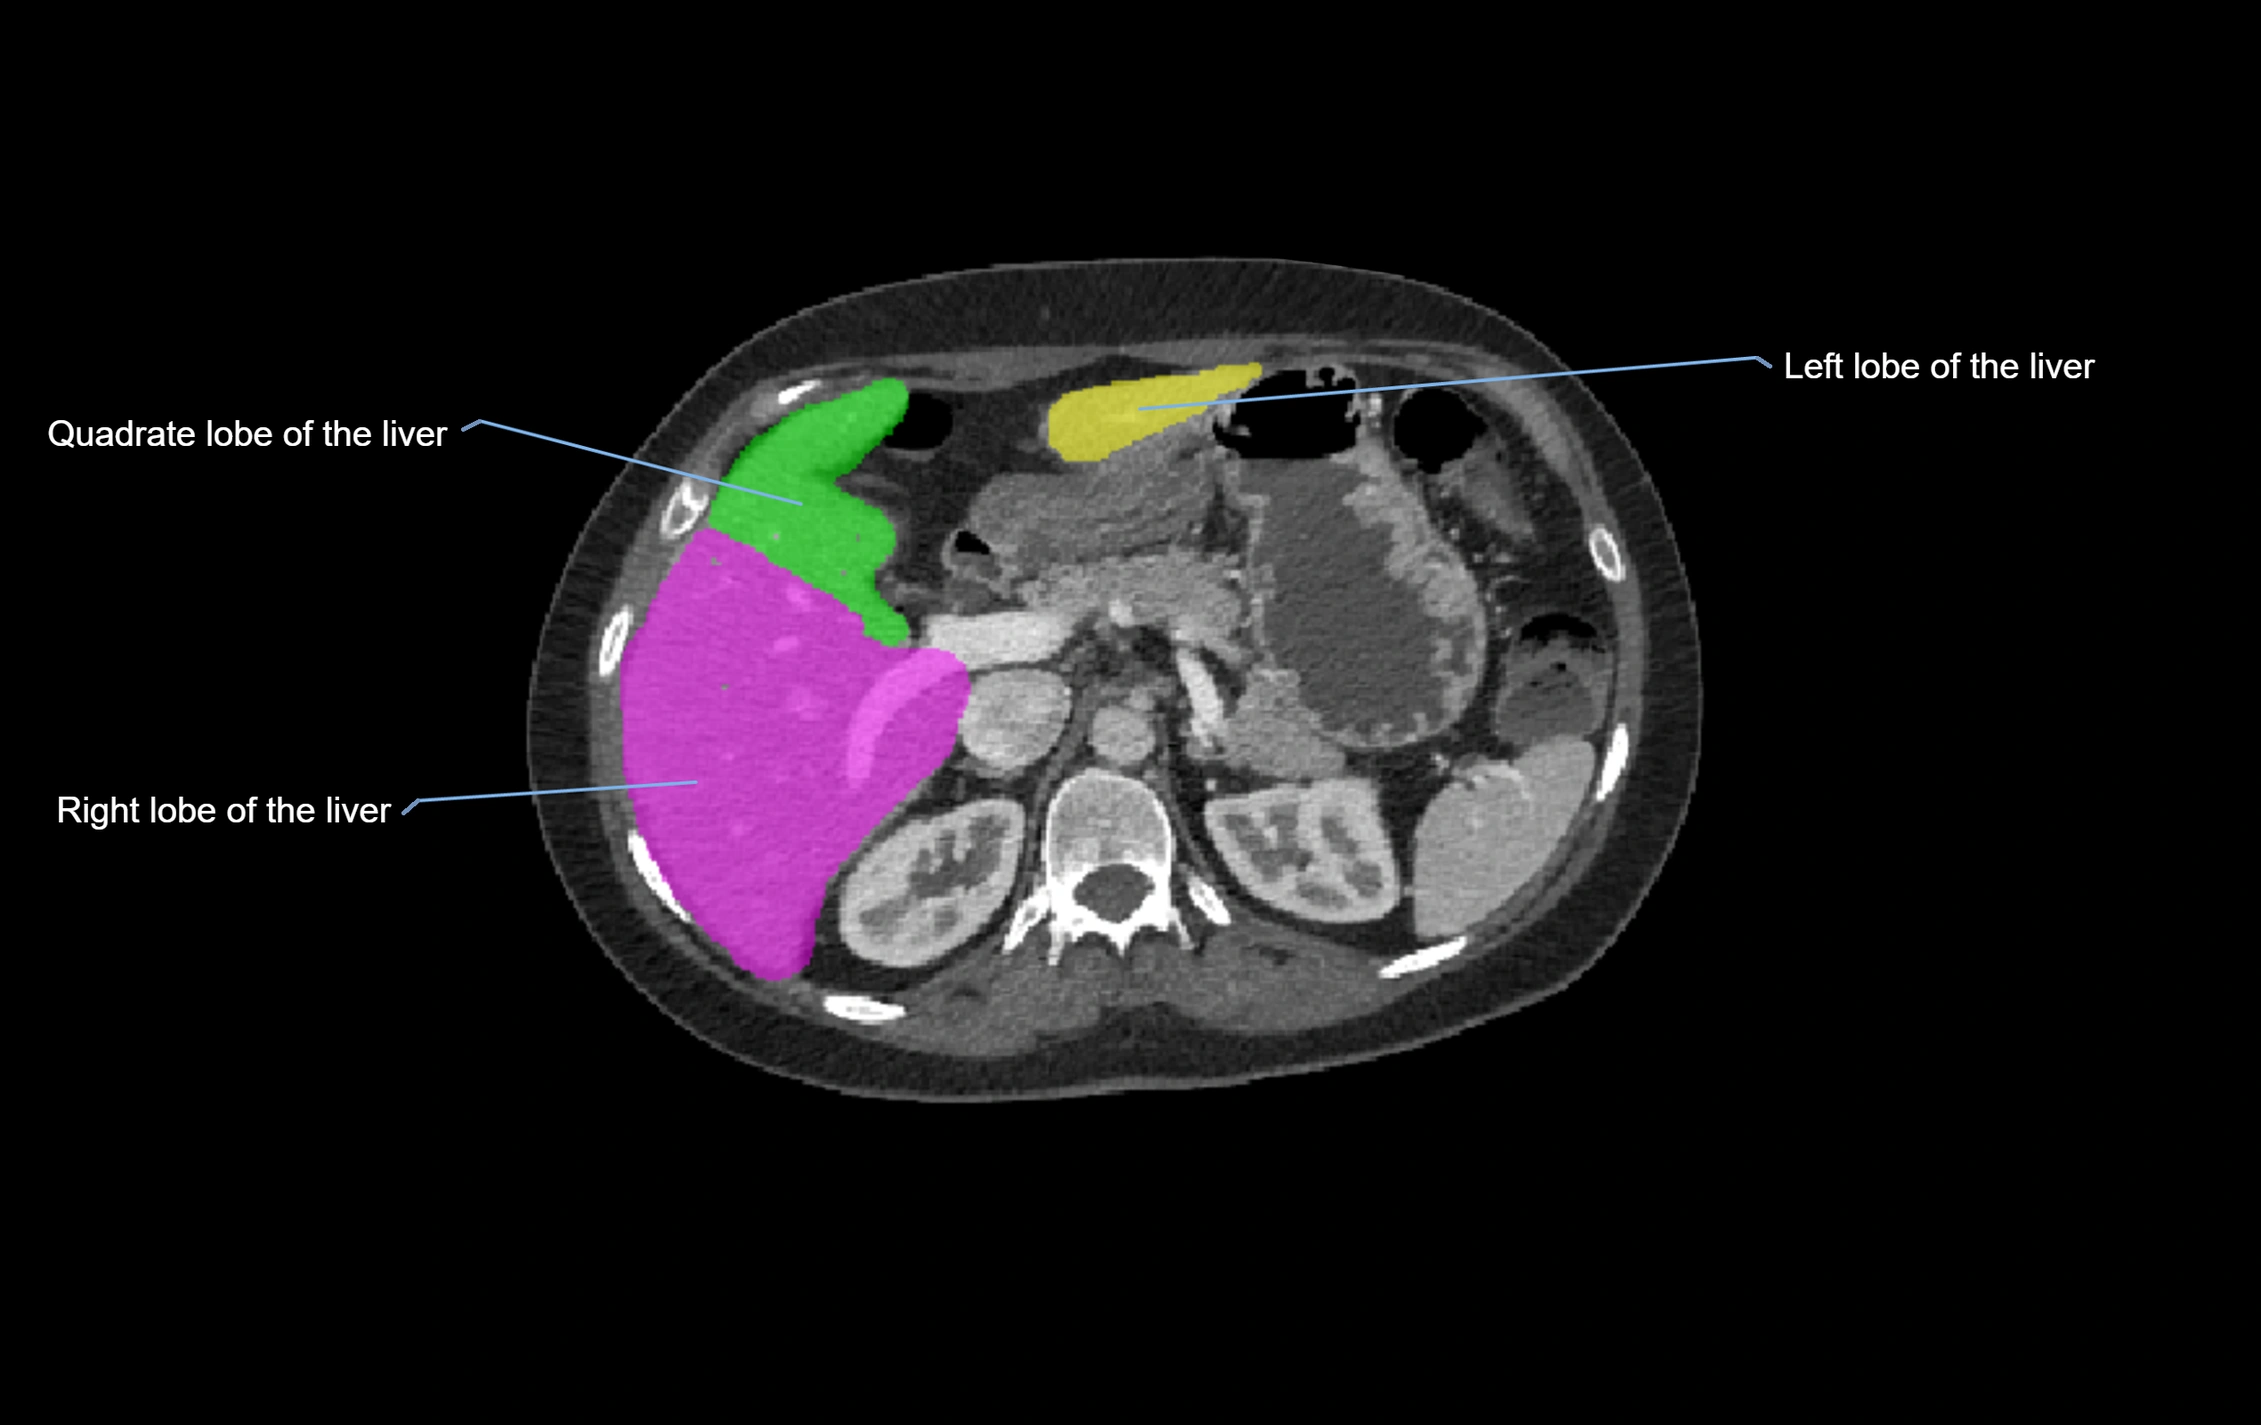

CT Image

image